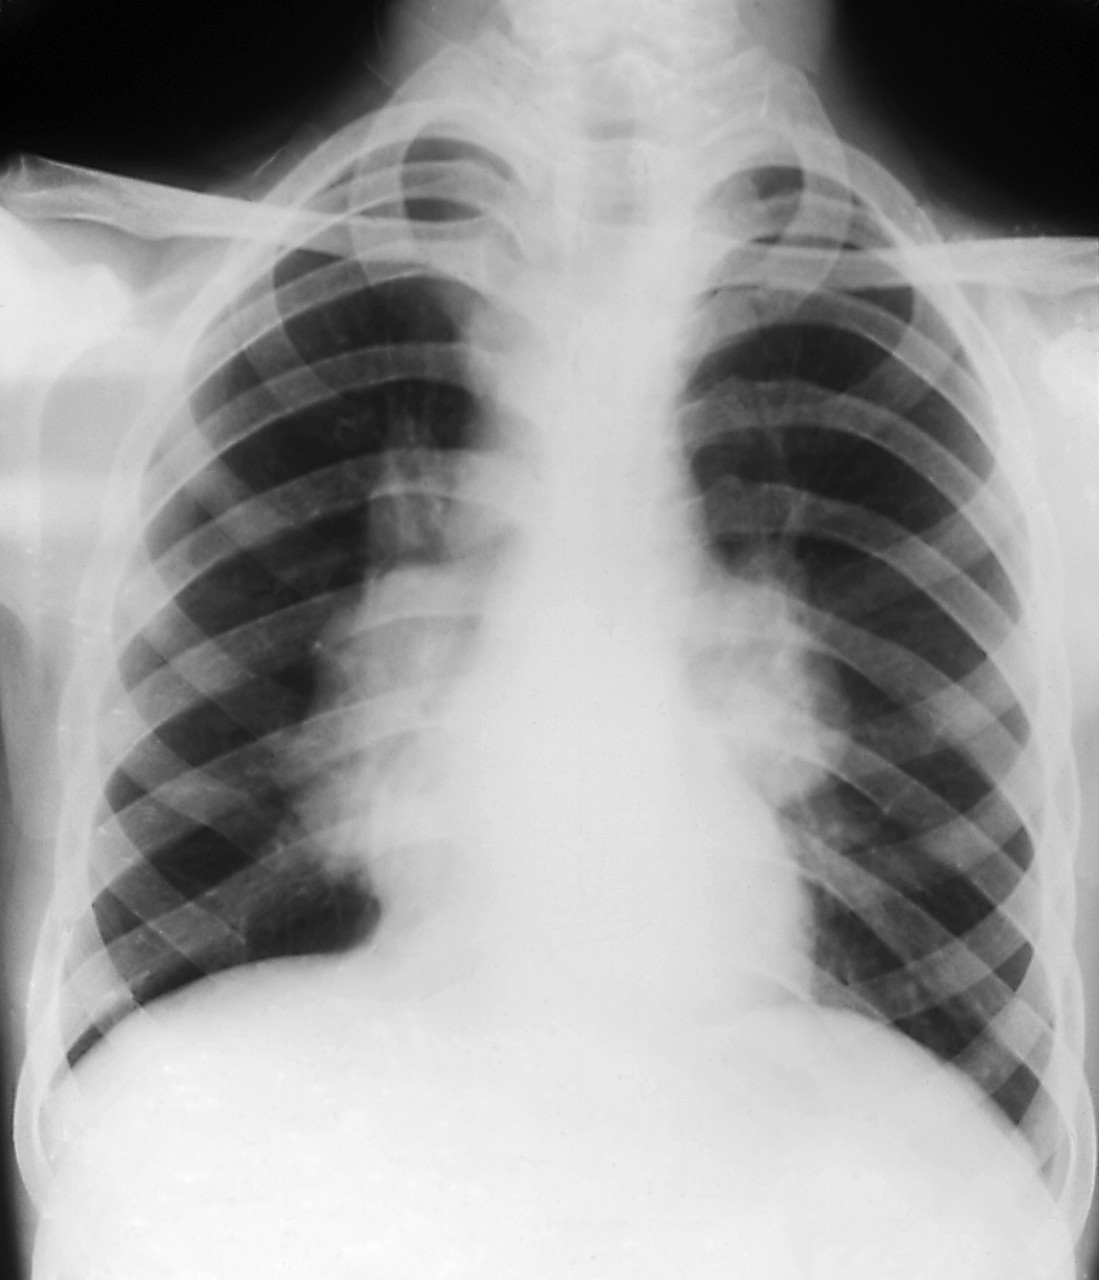

肺结节就是肺部CT影像学,针对肺部小病灶的描述性诊断,其中,80-90%以上直径小于2厘米,也就是说,近80 %的肺磨玻璃结节在就诊时,病灶都不到一个鹌鹑蛋的大小,是一种非常“迷你”的病变。